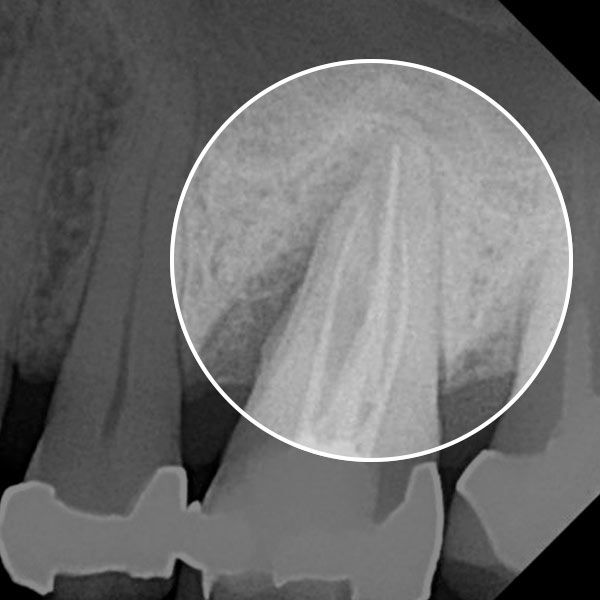

Before — Gum disease caused deep pockets to form.

After — The LANAP procedure restored a gum health.